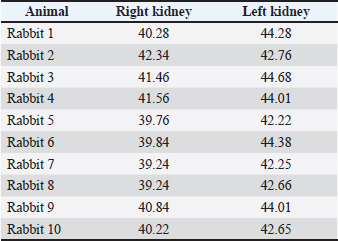

Fig. 23. Retrospective reconstruction of computed tomography data in Angio–Right and Left 1 mode in a rabbit (left side). (1) Extremitas cranialis; (2) Extremitas caudalis; (3) Left ureter (pars abdominalis); (4) Left ureter (pars pelvina); (5) Vesica urinaria; (6) Cecum; (7) Colon ascendens; (*) Aorta abdominalis. Statistical and metric analysesSoft tissue density was measured on pre-contrast CT scans to obtain objective data. The density of the right kidney was 40.28 ± 6.6 HU, and that of the left kidney was 43.36 ± 5.2 HU (Table 1). Table 1. CT values of rabbit kidneys in the HU.

CT anatomical dimensionsThe mean right kidney length was 3.45 ± 0.09 cm compared to 3.50 ± 0.07 cm for the left kidney. An excellent positive correlation was found between both kidney length (Y variable) and L2 length (X variable). The Pearson correlation coefficient was 0.957 for the right kidney and 0.961 for the left kidney at 95% CI. The length of both kidneys was strongly positively correlated with L2 length. The right and left kidney width was 2.36 ± 0.06 cm and 2.18 ± 0.07 cm, respectively, at p < 0.001. In all of the studied animals, the aforementioned specifics of the rabbit kidneys were found. The investigated organs had common features, including the cortex renis, medulla renis, eight papillae renales, well-developed pelvis renalis, macrodimensions, and soft tissue CT values. DiscussionThe presented information about the bilateral localization of both kidneys and the cranial position of the right kidney in relation to the left one confirmed Bensley’s (1948) thesis on the topography of these organs in rabbits. Furthermore, the retrospective reconstruction of CT data in Bones and Skin 1 and Bones and Skin 3 modes demonstrated the presence of well-formed renal papillae, which disagrees with the existing theories about the unipyramidal structure of the rabbit kidney (Bensley, 1948; Brewer, 2006; Dyce et al., 2010). The presence of well-developed capsula adiposa, capsula fibrosa, and distinctive cortex renis, medulla renis, and pelvis renalis in the Bones and Skin 3 reconstruction mode was added to the anatomical structure of rabbit kidneys (Bensley, 1948; Dyce et al., 2010). The presented data on the right kidney’s localization in the regio abdominis cranialis and that of the left kidney in the regio abdominis cranialis and regio abdominis media supplemented the information on the mutual placement of kidneys in the abdominal cavity. The observed localization of the right kidney in relation to the thoracic wall after Angio–Right and Left mode reconstruction agrees with the hypothesis on the intrathoracic localization of this organ in the rabbit (Harcourt-Brown, 2002). The presented evidence on the multipapillary structure of the two rabbit kidneys differs from the theory about the primitive structure of these organs (Dimitrov and Chaprazov, 2012a,b). On the other hand, the established bean-like shape and the sharply demarcated boundary between the cortex and medulla in the Bones and Skin 3 reconstruction correspond to the existing data on the structure of these organs (Dimitrov and Chaprazov, 2012a,b). We affirm that the medulla renis is built of renal papillae, which does not confirm the unipyramidal structure of the kidney, similar to that in rabbits and rodents (Vella and Donnelly, 2012). The eight papillae, the presence of a distinct crista renalis, the topographic location of the right kidney between Th13 (L1) and L2–L3, and the left kidney between L2 (L3) and L4 (L5) expand the theory (Barone, 2020) about the pyramidal structure of these organs, as well as their topographic location in the abdominal cavity. The obtained data are intravital and largely influenced by the inspiration and expiration phases. The eight papillae and smooth surfaces of both kidneys are consistent with published data describing the smooth and multipyramidal nature of the rabbit kidney (Stamatova-Yovcheva et al., 2022). Our results, showing the anatomical contact between the right kidney and the liver, the proximity of the right kidney with the duodenal pars descendens, the cecum and the colon ascendens, and finally the close proximity of the left kidney to the jejunum and colon descendens, support previously reported information for the kidneys in the rabbit (Barone, 2001; Hristov et al., 2006). We affirm that the used bone landmarks, e.g., Th13 (L1) and L2(L3) for the topographic position of the right kidney and L2 (L3) and L4 (L5) for the topography of the left kidney, are of higher informative value than the others (Barone, 2001; Hristov et al., 2006), according to which the ribs and intercostal spaces are reference anatomical landmarks. The proposed algorithm established the bilateral placement of both kidneys relative to the median plane and the cranial localization of the right kidney relative to the left one. Therefore, our study protocol differed significantly from those of previous studies (Tortora and Derrickson, 2012) that aimed to describe the mutual position of these organs in a dorsoventral aspect. The intravital pre-contrast and post-contrast CT scans offer wider ranges for the topography of the rabbit kidney—from Th13(L1) to L2(L3) for the right one and from L2(L3) to L4(L5) for the left one, compared to Th13-L2 that was previously described (Dimitrov and Chaprazov, 2012a,b). Prospective and retrospective reconstructions established the anatomical contact between the right kidney and the caudate liver lobe, which adds to the research algorithm applied in rabbits (Dimitrov and Chaprazov, 2012a,b). Given the appropriateness of rabbit kidneys in testing and monitoring various drugs, our hypothesis enables us to propose our results as an anatomical imaging model for studying important human diseases (Wu et al., 2003; Saeed et al., 2020). The intravital imaging results obtained are highly informative and can be used successfully in the interpretation and diagnosis of kidney diseases specific to this species (Percy and Barthold, 2007; Harcourt-Brown, 2013). The results accurately reflect the in vivo anatomical visualization of the rabbit kidney. They clearly show the structure of the renal parenchyma and the proximity of the organs to adjacent soft tissue structures. The topographic boundaries of the kidneys are presented in relation to the corresponding anatomical bone markers. Therefore, we propose CT as a modern, intravital, fast, and accurate method for imaging the kidneys, in support of its application in mammals (Yoon et al., 2010). The obtained pre-contrast and post-contrast anatomical images, based on the visualization of the capsula adiposa and capsula fibrosa, the clear demonstration of the renal pelvis, recesses, and crista renalis, the presence of distinct renal papillae, and finally the sharp definition between the kidney’s cortex and medulla were detailed and with high resolution. The presented facts support the hypothesis that CT is an appropriate and highly valuable method for visualizing parenchymal organs (Kleiter et al., 1999; Gielen et al., 2003; Yewon et al., 2023). In our opinion, the application of CT in the study of localization of the rabbit kidneys, their anatomical boundaries, adjacencies, including the contact between the right kidney and the caudate lobe, the intermediate attenuation degree and the lack of difference in the density between the cortex renis and the medulla renis adds up to the statements on the application of this technique in the rabbit (El-Ghazali et al., 2021). The soft tissue normoattenuated homogeneous images of both kidneys correspond to earlier reports on the kidneys in dogs (Serra-Gomez de la Serna et al., 2024). The crista renalis was hypoattenuated relative to the medulla renis in the precontrast study and hyperattenuated in the postcontrast study. This specific feature highlights the advantages of the algorithm used in this study, as well as the comprehensiveness of the results, which contrasts with the description of the crista renalis in dogs (Serra-Gomez de la Serna et al., 2024). The equal density of the cortex renis and medulla renis, as well as the absence of a distinct border between these two structures in prospective reconstructions and the presence of a border in retrospective reconstructions, is different from what was reported for the kidneys in dogs and cats (Oliveira et al., 2013). The CT imaging of the anatomical contact between the right kidney and the proc. caudatus on transverse sections was in wider limits (from Th13 to L3) compared to those described in previous studies on rabbits and chinchillas (Stamatova-Yovcheva et al., 2012; Stamatova-Yovcheva et al., 2013; Dilek et al., 2024), where the topographic relationship between the two organs was reported at the Th13 level. The existing correlation between the length of both rabbit kidneys and the length of the second lumbar vertebra, regardless of the biological subject’s body weight, agrees with a study conducted in dogs (Hoey et al., 2016). Our results, which describe a smaller length of the right kidney compared to the left one and a statistically significantly greater width of the right kidney relative to the left one, contradict the published data in dogs, which report higher values of these macrometric parameters for the right kidney compared to the left one (Atalar et al., 2017). Our data on the successful application of 3D reconstruction in various modes for anatomical imaging of the kidneys in rabbits contribute to the existing information for dogs (Atalar et al., 2017). CT is a definitive method for obtaining real and in vivo information about the macro-dimensions of rabbit kidneys. The obtained results are precise and accurate because the anatomic data are obtained using CT slices and reconstructions. Thus, CT is more accurate than conventional radiology when studying rabbit kidneys (Dorotea et al., 2016). The pre-contrast and post-contrast CT prospective reconstruction as well as 3D retrospective reconstruction allow the acquisition of highly informative anatomical imaging data. ConclusionThe applied CT algorithms demonstrated the topography of the studied organs in relation to the other abdominal organs and vessels and provided data about the renal cortex and medulla. Both kidneys of all examined rabbits were smooth and multi-papillary, with eight papillae. The obtained CT anatomical results can be used as appropriate models for investigation in veterinary and human medicine because the method is rapid and the ionization is minimized. All safety principles are considered. AcknowledgmentsWe would like to express our gratitude to Mrs. Daniela Ivanova, Department of Veterinary Surgery, Faculty of Veterinary Medicine, Trakia University, Stara Zagora, Bulgaria. Conflict of interestThe Authors declare that there is no conflict of interest. FundingThis research was funded by the Bulgarian Ministry of Education and Science in the framework of the Bulgarian National Recovery and Resilience Plan, Component “Innovative Bulgaria,” Project No. BG-RRP-2.004-0006-C02 “Development of research and innovation at Trakia University in service of health and sustainable well-being.” Authors' contributionsConceptualization: Avche Dineva, Kamelia Stamatova-Yovcheva, and Rosen Dimitrov. Validation: Diyana Vladova, David Yovchev, Ömer Gurkan Dilek. Methodology: Hristo Hristov, Vladi Nedev, Nikolay Goranov, and Tihomir Dinev. Data availabilityHowever, data are available from the authors upon reasonable request and with permission from the corresponding author, Kamelia Stamatova-Yovcheva. ReferencesAtalar., Koç, M., Alklay, A. and Hüseyin, H. 2017. Three-Dimensional Analysis with Computed Tomography of Kidneys in the Kangal Dogs. Dicle Üniv. Vet. Fak. Derg. 10(1), 24–29. Balikci, S., Banzato, T., Bellini, L., Contiero, B. and Zotti, A. 2016. Radiographic anatomy of dwarf rabbit abdomen with normal measurements. B. J. V. M. 19(2), 96–107. Barone, R. 2001. Chapitre V. In Anatomie comparée des mammifères domestiques. Barone Paris: Vigot, pp: 843–59. Barone, R. 2020. Chapitre, I.In Anatomie comparée des mammifères domestiques. Splanchnologie II. Barone. and R Paris: Vigot, pp: 3–80. Bensley, B. 1948. Rabbit Dissection. The Urogenital system.In Practical Anatomy of the Rabbit: an Elementary Laboratory Textbook in Mammalian Anatomy. Bensley Toronto: The University Press, pp: 127–33. Brewer. 2006. Biology of rabbit. J. Am. Assoc. Lab. Anim. Sci. 45(1), 8–24. Dilek, O.G., Dimitrov, R., Stamatova‐Yovcheva, K., Ersen, M., Yovchev, D., Sabancı, S.S. and Karakurum, E. 2024. Computed tomography and three-dimensional anatomical study of the liver in the chinchilla (Chinchilla lanigera). Anat. Histol. Embryol. 53(2), e13025; doi: 10.1111/ahe.13025 Dimitrov, R. and Chaprazov, T. 2012. An anatomic and contrast enhanced radiographic investigation of the rabbit kidneys, ureters and urinary bladder. Rev. Med. Vet. 163(10), 469–474. Dimitrov, R., Kostov, D., Stamatova, K. and Yordanova, V. 2012. Anatomotopographical and morphological analysis of normal kidneys of rabbit (Oryctolagus cuniculus). Trakia J. Sci. 10(2), 79–84. Dyce, K., Sack, W. and Wensing, C. 2010. The urogenital apparatus.In Textbook of Veterinary Anatomy. Singh, B.W Philadelphia: W. B. Saunders Company, pp: 167–215. El-Ghazali, H.M., Ammar, S.M.S., Mohamed, S.K.A., Gomaa, M. and Ibrahim, S.M.E. 2021. Topographic and morphometric study on the kidneys of Balady rabbit enhanced by ultrasonographic, radiographic and computed tomography Scan. Int. J. Vet. Sci. Res. 11(1), 28–36. Farhana, S. and Wibowo, F.A. 2019. Anatomical and histological study of male uropoetic organs of common rabbit (Oryctolagus cuniculus). In Proc. Internat. Conf. Sci. Engin. 2, 149–152. Gielen, I., Caelenberg, A. and Van Bree, H. 2003. Computed Tomography (CT) in small animals. Part 1. Technical Aspects. Vlaams Diergeneeskd. Tijdschr. 72(3), 158–167. Harcourt-Brown, F.M. 2013. Diagnosis of renal disease in rabbits. Vet. Clin. Exot. Anim. 16(1), 145–174. Hoey, S.E., Heder, B.L., Hetzel, S.J. and Waller, K.R. 2016. Use of computed tomography for measurement of kidneys in dogs without renal disease. Small. Animals. &. Exotics. 248(3), 282–287. Hristov, H., Kostov, D. and Vladova, D. 2006. Topographical anatomy of some abdominal organs in rabbits. Trakia. J. Sci. 4(3), 7–10. Ji, Y., Hwang, G., Lee, S.J., Lee, K. and Yoon, H. 2023. A deep learning model for automated kidney calculi detection on non-contrast computed tomography scans in dogs. Front. Vet. Sci. 10, 1236579; doi:10.3389/fvets.2023.1236579 Kleiter, M., Henninger, W., Hirt, R. and Lorinson, D. 1999. Portosystemic shunt in a dog - computed tomography as a successful imaging method. Wien. Tierarztl. Monat. 86, 64–70. Oliveira, D.C., Costa, L.A.V.S., Silva, I.C.C., Teixeira, M.W. and Costa, F.S. 2013. Quantitative computed tomography of the renal cortex in healthy dogs and cats. Arq. Bras. Med. Vet. Zootec. 65(4), 1253–1256. Percy, D. and Barthold, S. 2007. Rabbit.In Pathology of laboratory rodents and rabbits. Percy, D. and Barthold, S Oxford: Blackwell Publishing, pp: 253–308. Saeed, M.I., Nicklas, R.D., Kumar, V., Kapoor, R. and Gani, I.Y. 2020. Severe intraoperative anaphylaxis related to thymoglobulin during living donor kidney transplantation. Antibodies 9(3), 43. Serra‐gomez De La Serna, B., Schiborra, F. and Marwood, R. 2024. Prevalence of canine renal crest hyperattenuation in precontrast computed tomography. Vet. Radiol. Ultrasound. 65(4), 352–358. Stamatova Yovcheva, K., Dimitrov, R., Toneva, Y., Yonkova, P., Kostov, D., Rusenov, A., Uzunova, K. and Yordanova, V. 2013. Helical computed tomography application in rabbit liver anatomy: comparison with frozen cross-sectional cuts. Turkish. J. Vet. Anim. Sci. 37(5), 553–558. Stamatova-Yovcheva, K., Dimitrov, R., Dilek, Ö. G., Tsandev, N., Kostadinov, G., Russenov, A. and Hristov, Ts. 2022. A case of multipyramidal kidneys with smooth surface in a New Zealand white rabbit. MAE Vet. Fak. Derg. 7(1), 58-61. Stamatova-Yovcheva, K., Dimitrov, R., Yonkova, P., Russenov, A., Yovchev, D. and Kostov, D. 2012. Comparative imaging anatomic study of domestic rabbit liver (Oryctolagus cuniculus). Trakia J. Sci. 10(1), 57–63. Vella, D. and Donnelly, T.M. 2004. Basic Anatomy, Physiology, and Husbandry.In Ferrets, Rabbits, and Rodents. Clinical Medicine and Surgery. Quesenberry, K. and Carpenter St. Louis: Elsevier Saunders, pp: 157–73. Wu, J., Ge, X. and Fahy, G.M. 2003. Ultrarapid nonsuture mated cuff technique for renal transplantation in rabbits. Microsurgery 23(4), 369–373. Yoon, W., Lee, M.Y., Ryu, J.M., Moon, Y.J., Lee, S.H., Park, J.H., Yun, S.P., Jang, M.W., Park, S.S. and Han, H.J. 2010. Multidetector row computed tomography evaluation of the micropig kidney as a potential renal donor. J. Vet. Sci. 11(1), 9–13. | ||